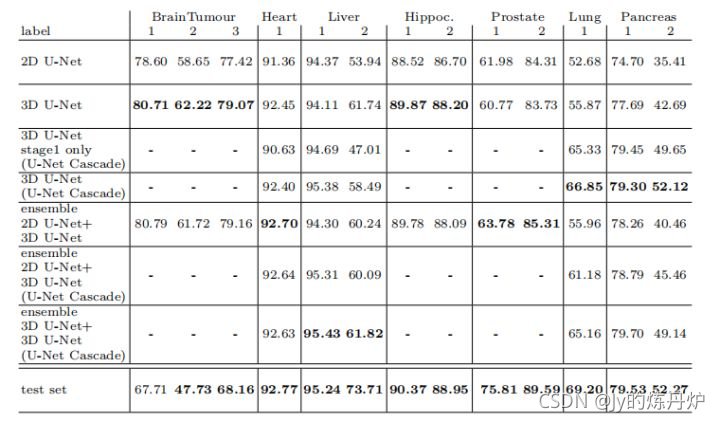

8. 结果